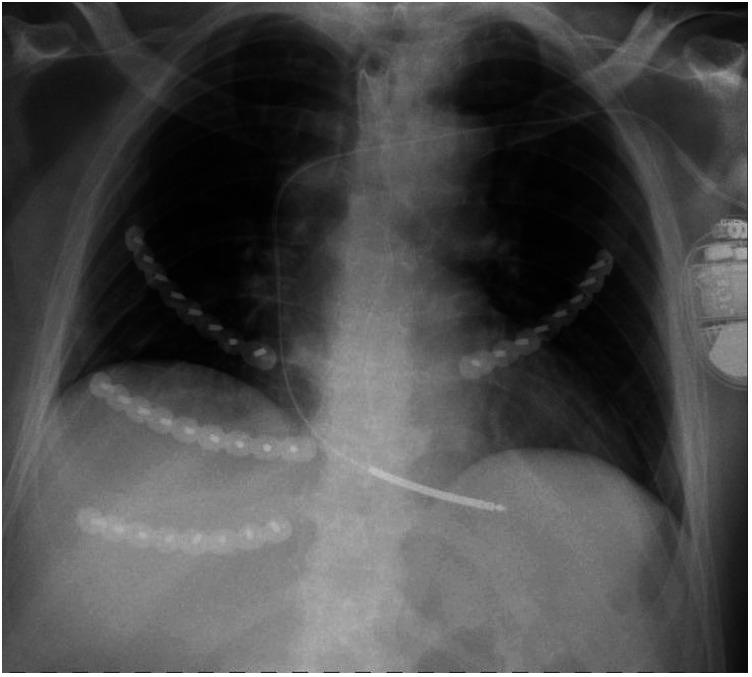

Outcomes after fixation of rib fractures sustained during cardiopulmonary resuscitation: A retrospective single center analysis.

Historically rib fractures have been typically treated non-operatively. Recent studies showed promising results after osteosynthesis of rib fractures in trauma patients with flail segments or multiple rib fractures. However, there is a paucity of data on rib fixation after cardiopulmonary resuscitation (CPR). This study evaluated the outcomes of patients who received rib fixation after CPR.

Nineteen patients were included with a mean age of 66.8 years. The mean number of fractured ribs was ten, seven patients additionally had a sternum fracture. Pneumonia occurred in 15 patients (74%), of which 13 were diagnosed preoperatively and 2 post-operatively. Six patients developed a postoperative pneumothorax, none of which required revision surgery. One patient showed persistent flail chest after rib fixation and required additional fixation of a concomitant sternum fracture. One infection of the surgical site of sternal plate occurred, while no further surgery related complications were reported. Mean EQ-5D-5L was 0.908 and the average EQ VAS was 80. One patient reported persisting dyspnea.

To date, this is the largest reported cohort of patients who received rib fixation for fractures sustained during CPR. No complications associated with rib fixation were reported whereas one infection after sternal fixation did occur. Current follow-up demonstrated a good long-term quality of life after fixation, warranting further studies on this topic. Deeper knowledge on this subject would be beneficial for a wide spectrum of physicians.